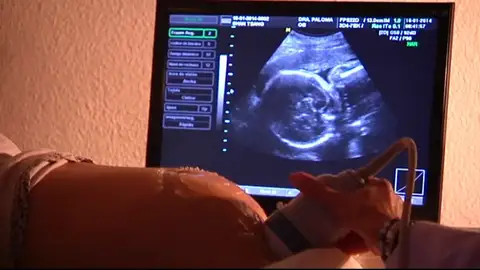

Un bebé ha muerto en un parto que no tuvo asistencia médica. Los padres decidieron que la madre diera a luz en su casa, pero el niño venía de nalgas. Este caso reabre el debate sobre los partos naturales sin control médico.